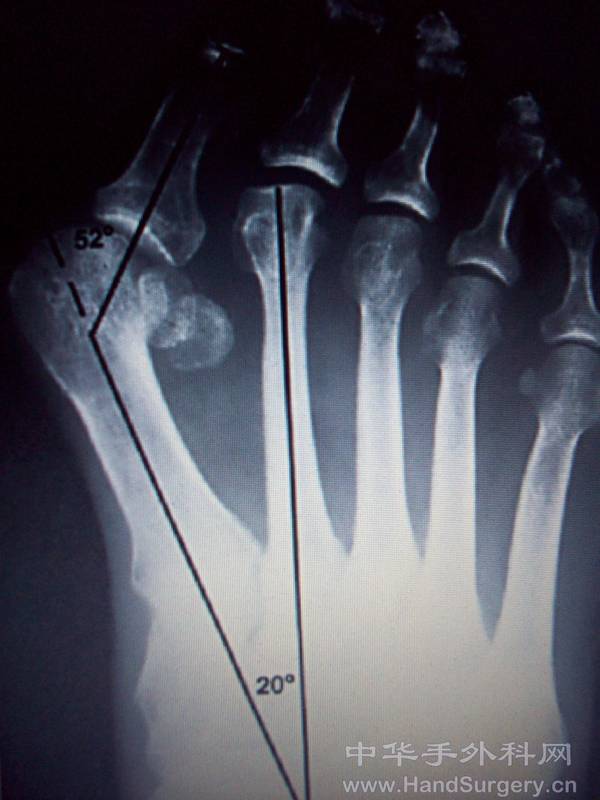

拇外翻的病因:

遗传、性别、生活习惯、关节疾病等因素

拇外翻病理改变:

病变发生在第一跖趾关节

第一跖骨内翻,跖骨头向内移位,而籽骨在拇收肌、拇短屈肌和跖横韧带等结构的牵拉下维持原位,籽骨相对于跖骨头向外发生移动,跖骨头跖侧骨嵴被磨平籽骨失去了跖趾关节在屈伸中的滑车作用,籽骨的外移将会牵拉拇趾近节趾骨发生旋转。

其他两个涉及第一跖趾关节的解剖学改变也可以引起拇外翻

第一个改变为跖骨头关节面偏斜,其偏斜的角度被称为跖骨远端关节固角(DMAA)

第二个改变为趾近节趾骨基底的关节角相对于其纵轴出现偏斜,其偏斜角度被称为趾骨近端关节固角(PAA)